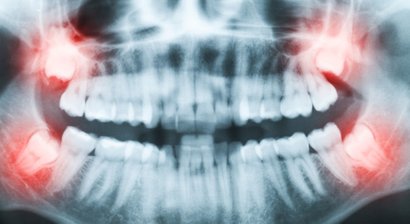

Weisheitszahnentfernung

Weisheitszähne brechen in der Regel erst im Erwachsenenalter durch. Zu dieser Zeit verfügen sie jedoch häufig über zu wenig Platz im Gebiss. Die Folge: Sie liegen schräg und können nicht normal wachsen. In vielen Fällen bleiben die Weisheitszähne auch vollst&a...